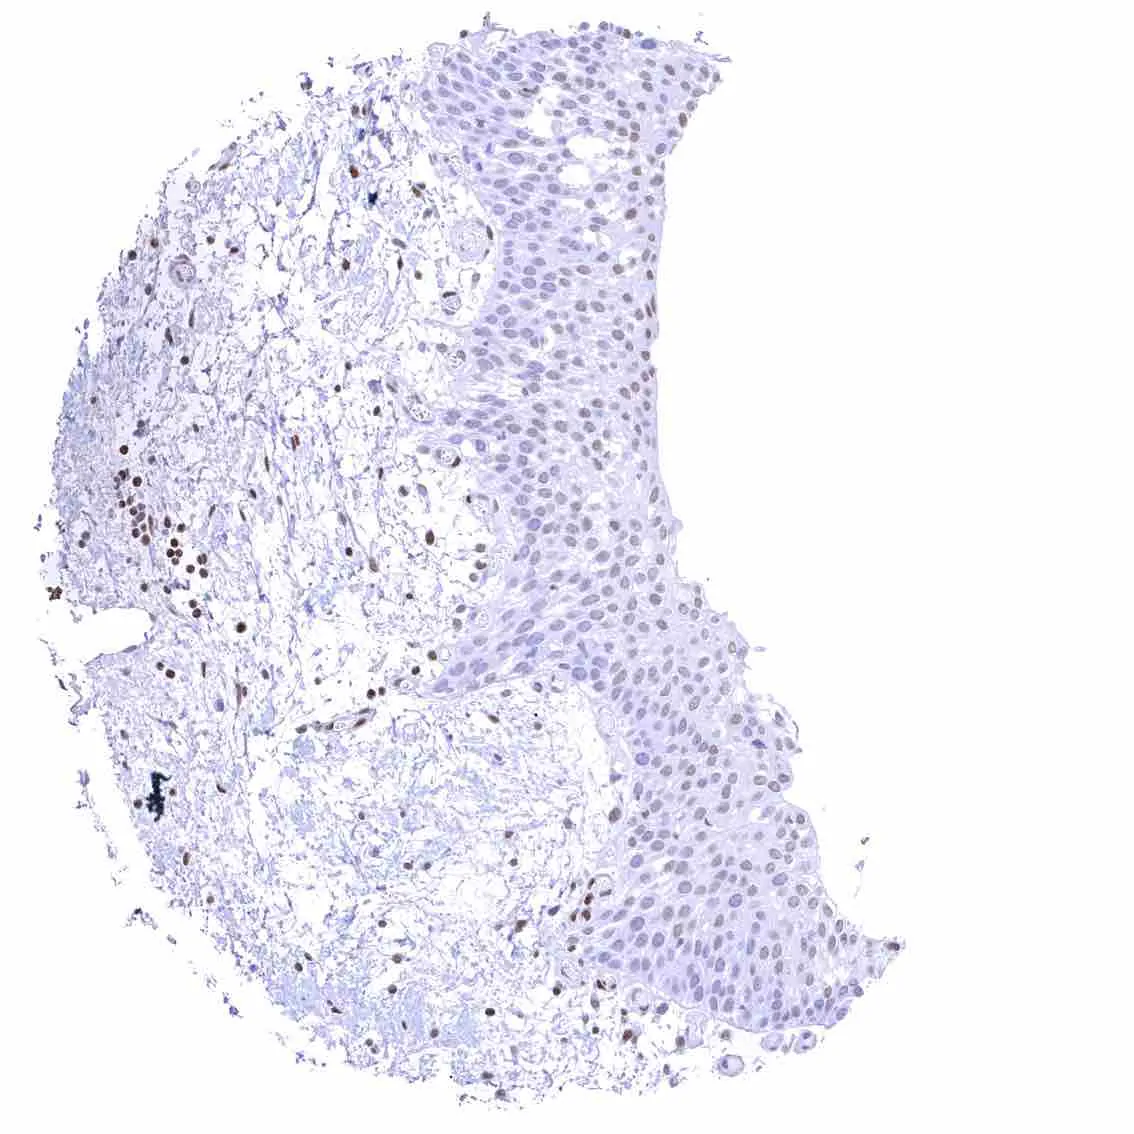

Tonsil – Strong nuclear p27 staining of a significant subset of cells, especially in the interfollicular area. Nuclear staining of squamous epithelial cells predominates in the more mature cell layers (top 50_ of the epidermis).

Tonsil, surface epithelium – Strong nuclear p27 staining of a significant subset of cells, especially in the interfollicular area. Nuclear staining of squamous epithelial cells predominates in the more mature cell layers (top 50_ of the epidermis).